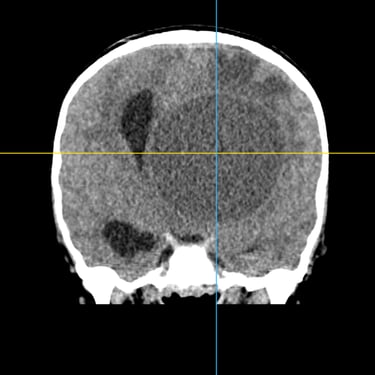

El absceso cerebral es una infección localizada del parénquima cerebral que produce acumulación de pus e inflamación, generando cefalea, fiebre, alteración del estado de conciencia o déficit neurológico focal. El diagnóstico temprano es fundamental para evitar complicaciones graves. La tomografía cerebral con contraste es el estudio de elección inicial, ya que permite visualizar una lesión hipodensa con realce en anillo característico. Posteriormente, la resonancia magnética complementa la evaluación. El tratamiento combina antibioticoterapia dirigida y, en casos seleccionados, drenaje quirúrgico o resección. La detección oportuna mediante imágenes mejora significativamente el pronóstico del paciente.